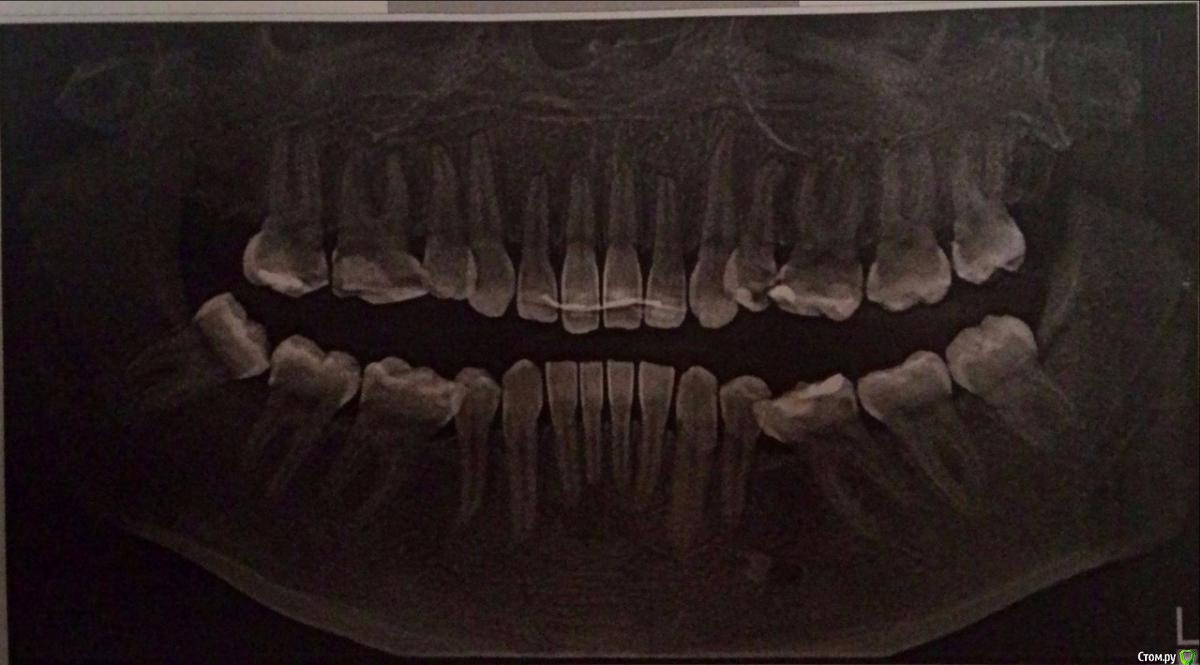

Yana guapa Опубликовано 27 декабря, 2015 Поделиться Опубликовано 27 декабря, 2015 1. какие основные жалобы сейчас?? 2. если Вы хотите предпринять действия , чтобы не ухудшилось состояние пародонта и ВНЧС(?) , то это невозможно без полноценного лечения с созданием качественных контактов зубных рядов. КАКИМ способом это будут достигаться (с хирургией или без) это надо будет решать (снимок ТРГ-размыт, остальных фото нет). 3. на ОПТГ - верхушки корней некоторых зубов уже укорочены (после первого лечения). Что будет с ними после второго лечения? Ссылка на комментарий

Yana guapa Опубликовано 27 декабря, 2015 Поделиться Опубликовано 27 декабря, 2015 А чем сулит "укорочение верхушек", 1.если повторно лечиться - то они могут еще сильнее укоротиться, и потом зубы могут просто выпасть)) 2. http://forum.stom.ru/topic/4655-patcientam/3. обратите внимание, как сильно наклонены нижние восьмерки, особенно справа (возникает гипер контакт, идет дополнительная излишняя нагрузка на сустав)4. на ТРГ в области сустава - белое пятно ( снимок неинформативный)5. имеет ли смысл делать новые снимки? решать Вам, если планируете полноценное новое лечение (но для этого Вам нужно найти доктора, который возьмет Вас на лечение и он же направит на нужные снимки) Ссылка на комментарий